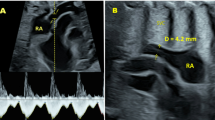

Recent data suggest that umbilical venous perfusion of the fetal liver has an important influence on fetal growth and postnatal liver function, and that maternal factors in late pregnancy modify this circulation. In a longitudinal study of 160 low-risk pregnancies, we determined how umbilical and portal venous blood flows to the fetal liver changed during gestation, and examined the hypothesis that maternal body mass index and pregnancy weight gain influenced fetal liver blood flows. We measured blood flows in the umbilical and portal veins, left portal branch, and ductus venosus using ultrasound. Normalizing for estimated fetal weight, fetal liver total venous blood flow fell from 84 to 57 mL · min−1 · kg−1 during 21–39 wk of gestation; toward term the portal contribution increased (from 14 to 20%) and the umbilical contribution fell, whereas distribution between the left and right liver lobes was stable, 60%/40%. Greater flow of nutrient-rich umbilical venous blood to the liver was associated with higher birth weight and neonatal ponderal index. Maternal body mass index was not related to fetal liver blood flows, but low pregnancy weight gain strongly influenced flow distribution between the right and left liver lobes, sparing the left lobe and increasing the difference between lobes by 16%.